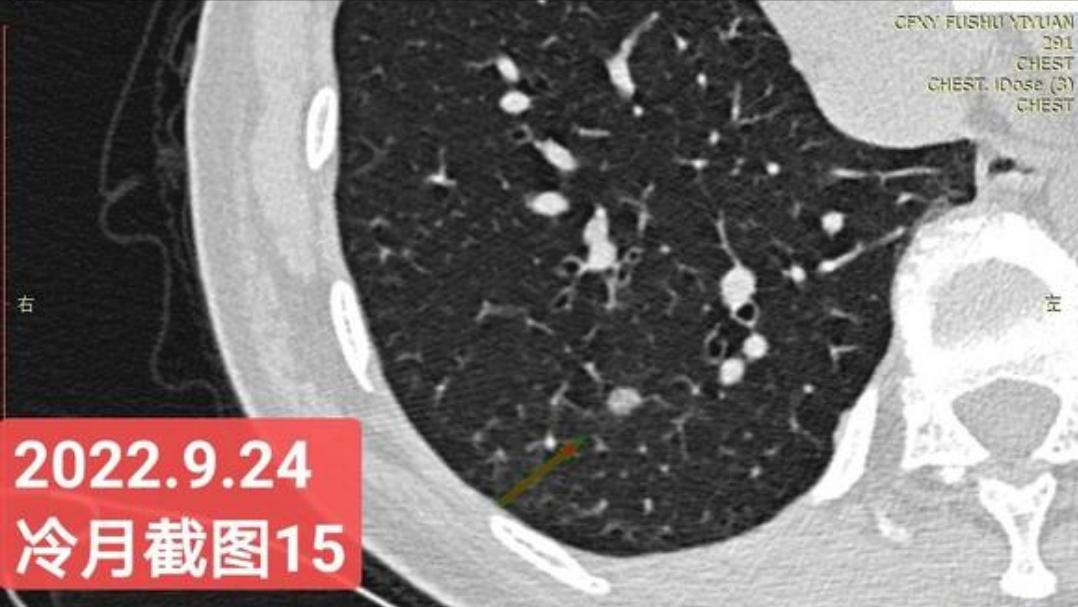

我是21年7月做肺部CT,报告给报出0.5厘米肺结节。(但大夫说,20年就已经有那个肺结节了,因为小,报告没给报)。自发现肺结节后,吃了四个月中药,结节没有缩小,反而增大了。今年8月1日开始到现在,又吃了近两个月的蒙药了。 结节还是没有缩小,反而在增大。21年7月到现在,复查过3次肺部CT了。结节一直在增大。最近一次复查时间是2022年9月24日。

上次找戴主任贴吧咨询过,主任说我右肺下叶那个结节高危,距离上次CT,到现在三个月复查肺部CT。所以9月24日又复查做了肺部CT。

右下肺结节高危,肺窗已经到亚实性阶段CTR>0.5,纵膈窗可见实性,目前已经不属于异质混磨,而且PSN亚实性结节。